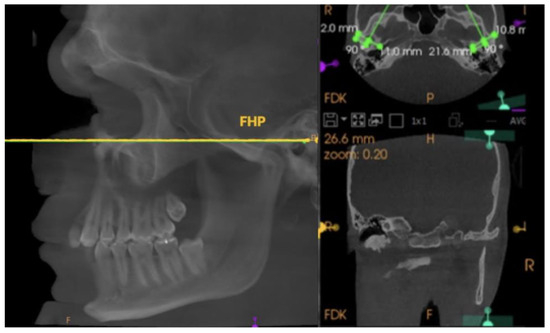

書籍詳細「藤本研修会 Standard Textbook 2 Occlusion。Amazon.com: Functional Occlusion: From TMJ to Smile Design。91INEEHBPmL._UF350,350_QL50_.jpg。藤本研修会の咬合、補綴のテキストブックです。Comparison of Condylar Guidance in Opening and Protrusion。裁断済みの為お安くなっています。新品 最新刊 プロメテウス解剖学コアアトラス 第4版。スレ等ありますので神経質な方はご遠慮下さい。新・徒手筋力検査法 原著第10版[Web動画付]。